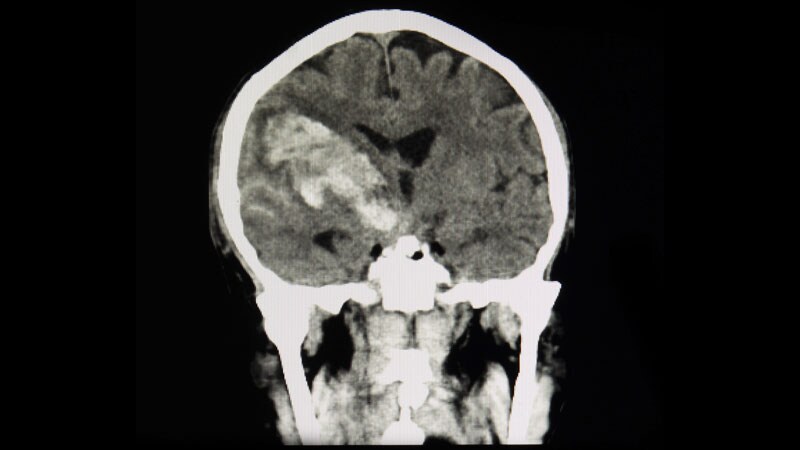

ISC 2023Thrombectomy Benefits Stroke With Large Core Volumes: SELECT2A new international trial has shown large benefits of thrombectomy in patients with ischemic strokes with a large core volume, which should lead to a change in clinical practice.

Tenecteplase for Stroke Linked to Reduced ICH RiskA new study shows use of tenecteplase is associated with a lower risk of symptomatic intracranial hemorrhage compared with

the standard alteplase in patients who have suffered stroke.